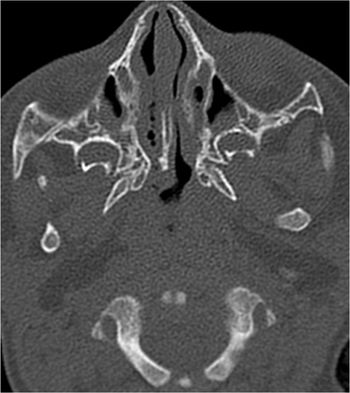

CT scan diagnoses right choanal atresia in 6-month-old male child. Pre-surgical evaluation. Non-enhanced axial CT scan of paranasal sinuses.